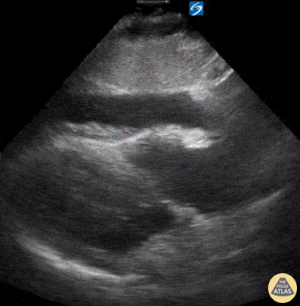

VCI (İnferior vena cava)

• IVC / Subkostal pencere